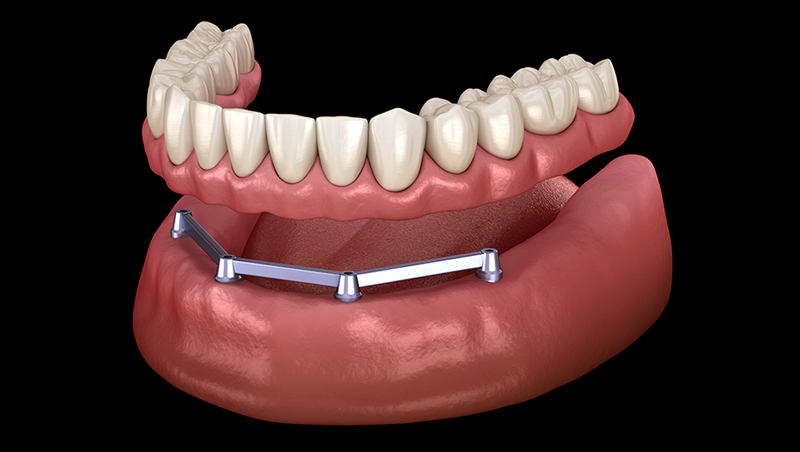

バータイプ

複数のインプラントをバーで連結し、その上に入れ歯を固定する方法です。安定性が高く、咬合力を分散しやすいため、強く咬みたい方に適しています。